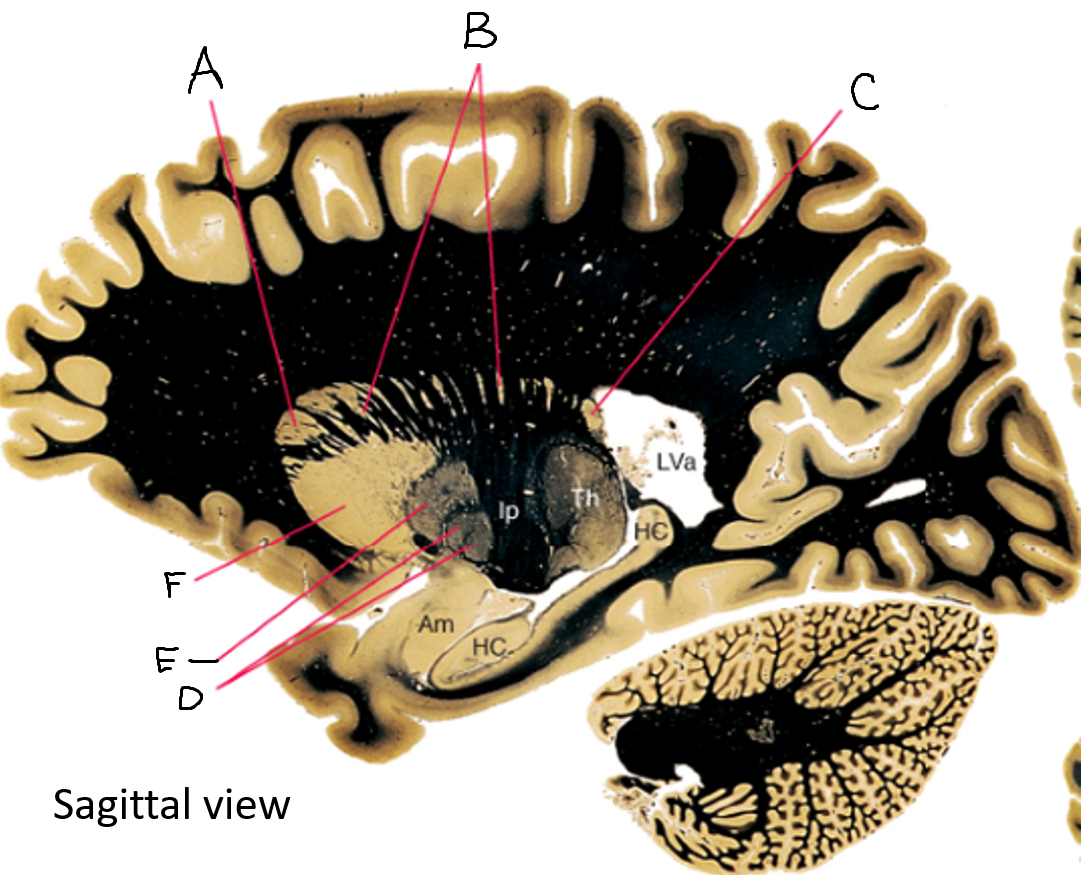

caudate nucleus head

A

Putamen

B

caudate nucleus tail

C

Lateral ventricle

D

caudate nucleus body

E

internal capsule

F